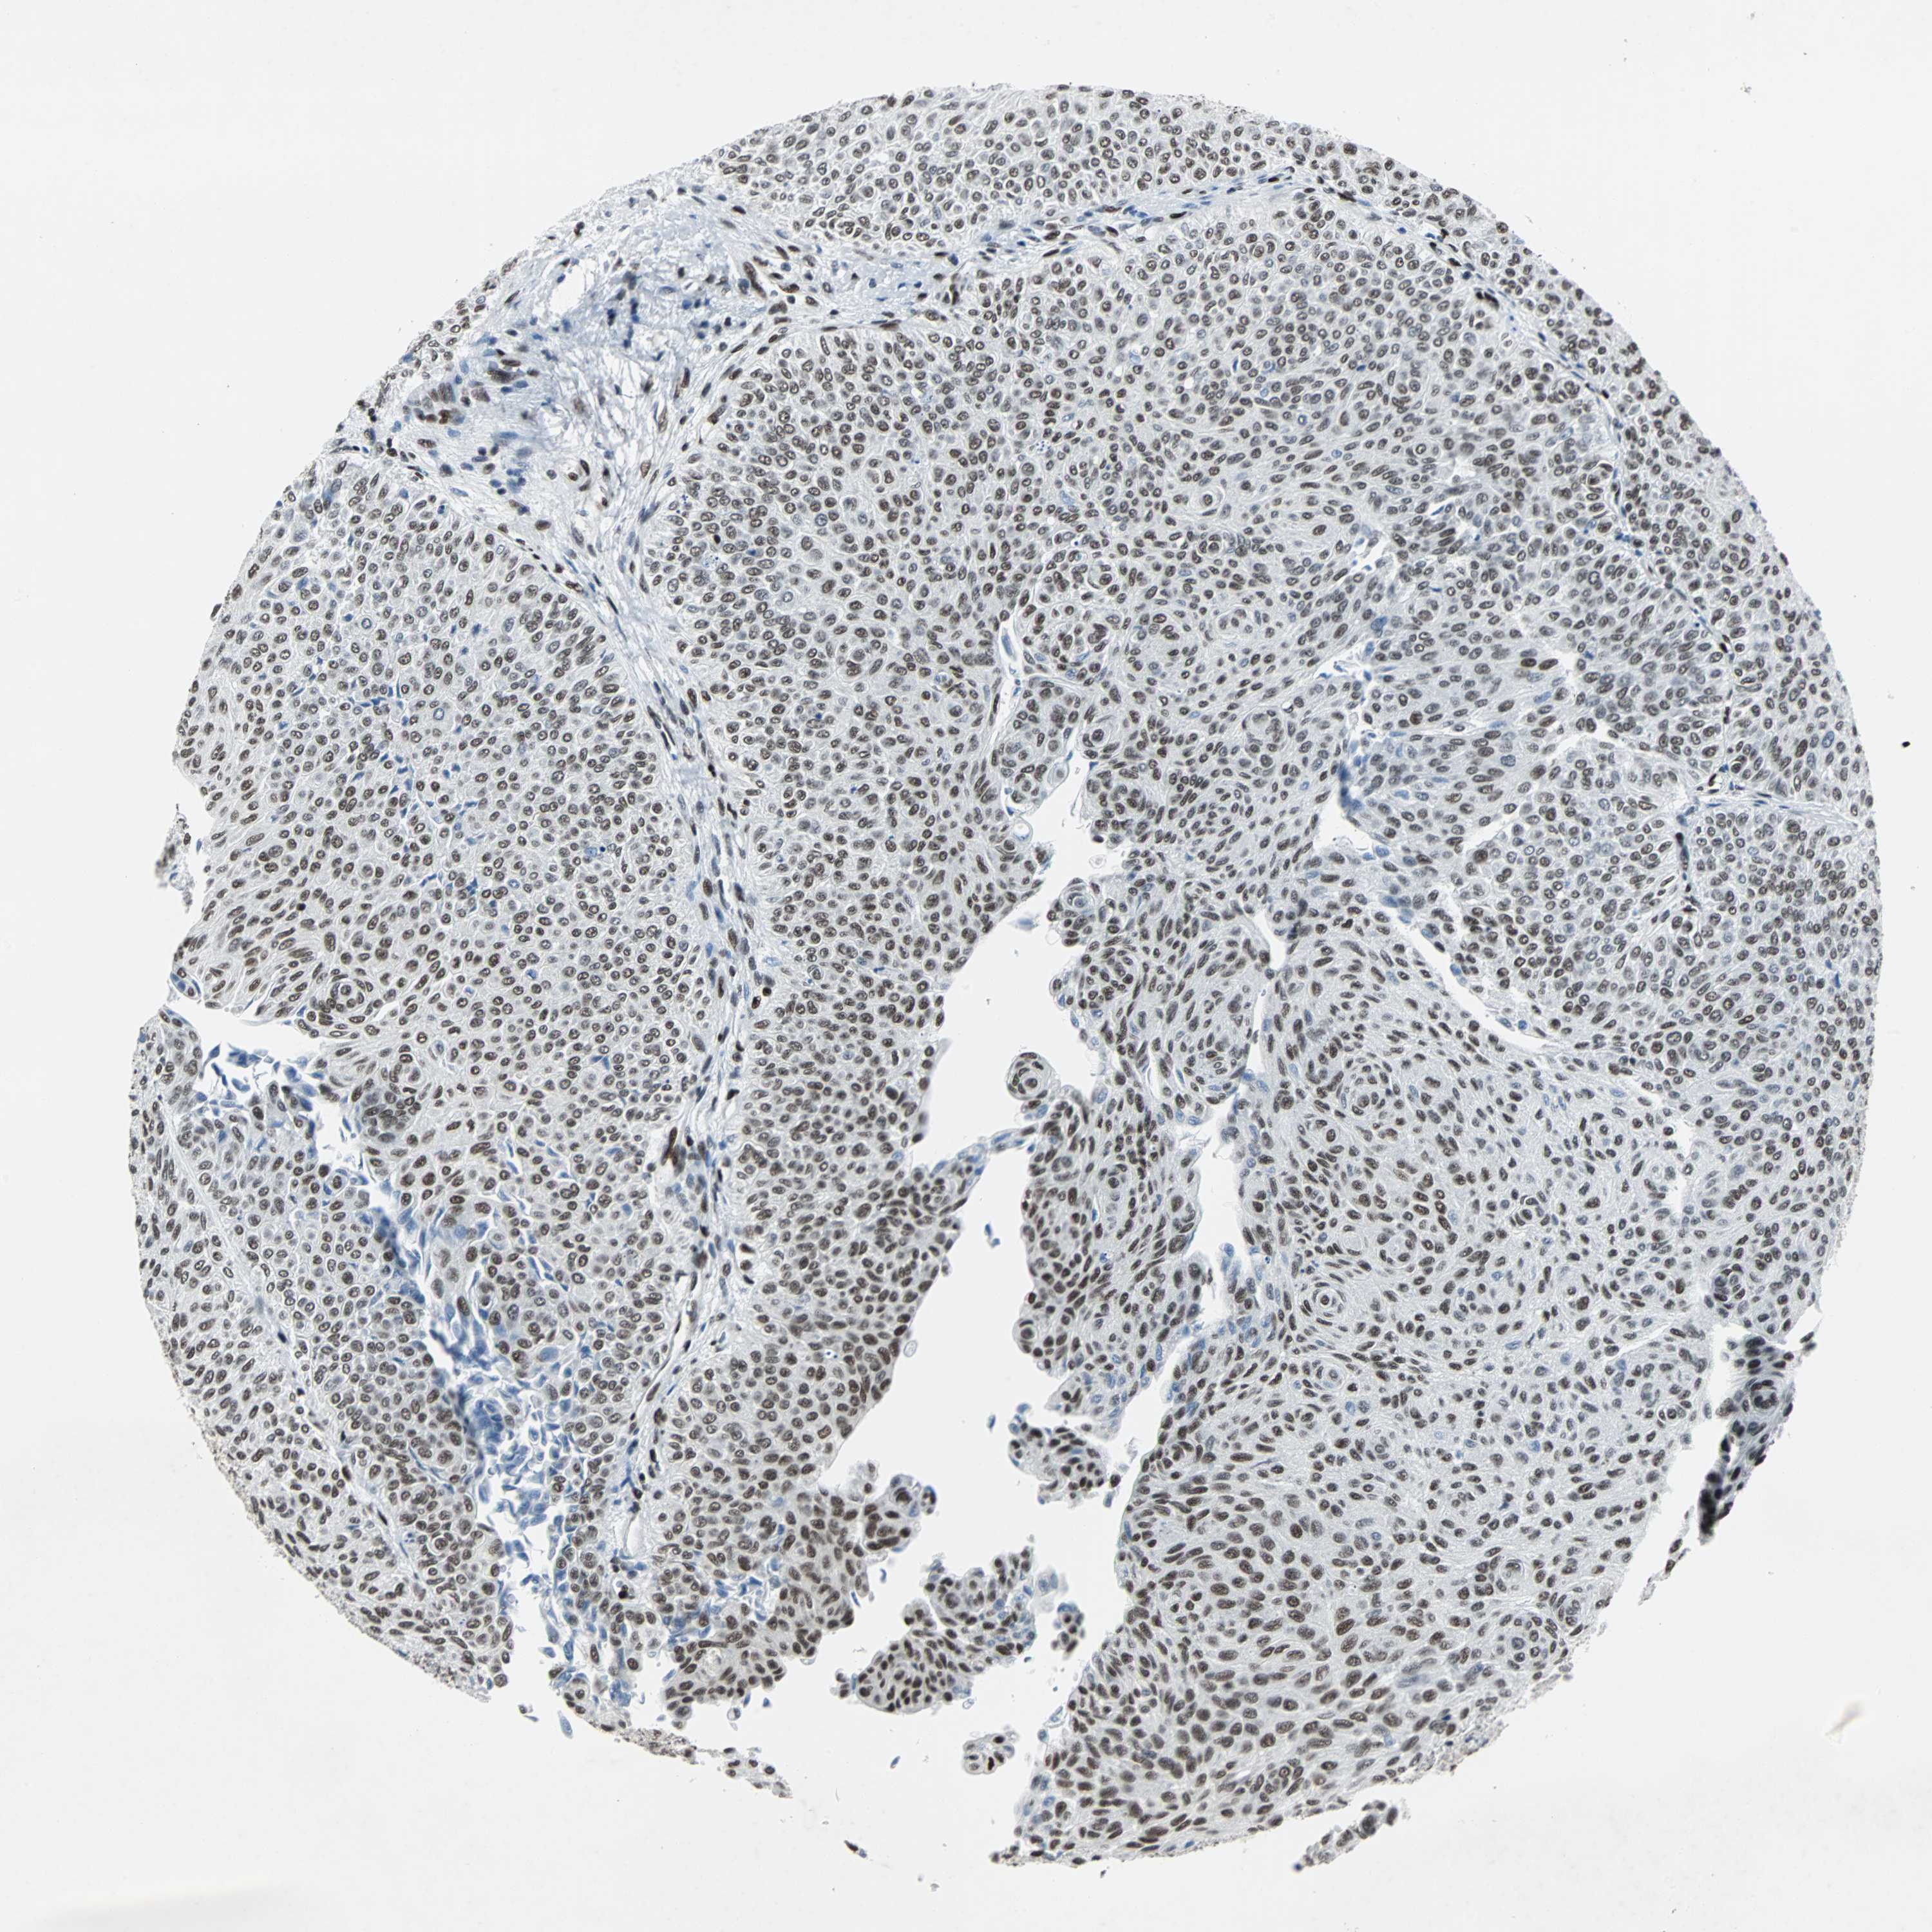

UROTHELIAL CANCER - Protein expressioni

A mouse-over function shows sample information and annotation data. Click on an image to view it in a full screen mode. Samples can be filtered based on level of antibody staining by selecting one or several of the following categories: high, medium, low and not detected. The assay and annotation is described here.

Note that samples used for immunohistochemistry by the Human Protein Atlas do not correspond to samples in the TCGA dataset.

Antibody stainingi

Antibody staining in the annotated cell types in the current human tissue is reported as not detected, low, medium, or high, based on conventional immunohistochemistry profiling in selected tissues. This score is based on the combination of the staining intensity and fraction of stained cells.

Each image is clickable and will lead to virtual microscopy that enables deeper exploration of all samples and also displays staining intensity scores, fraction scores and subcellular localization as well as patient and tissue information for each sample.

Antibody HPA004807

Antibody HPA007114

Staining

High

Medium

Low

Not detected

Intensity

Strong

Moderate

Weak

Negative

Quantity

>75%

75%-25%

<25%

None

Location

Nuclear

Cytoplasmic/membranous

Cytoplasmic/membranous,nuclear

Urothelial carcinoma, High grade

Urothelial carcinoma, Low grade